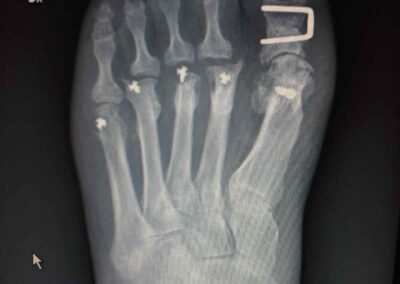

Le tecniche chirurgiche a nostra disposizione sono molteplici e vanno individualizzate sul paziente. Tra le varie preferisco la osteotomia distale del primo metatarso fissata con adeguati mezzi di sintesi preferibilmente in titanio associata al rilascio della capsula sul versante laterale. In alcuni casi difficili può essere indicato associare anche una osteotomia della prima falange dell’alluce oltre a trattamenti diretti alla correzione di eventuali griffe digitali associate.

In questi frequenti casi che di solito riguardano il secondo dito pratico una resezione della testa della prima falange associando frequentemente una capsulotomia dorsale della seconda metatarso-falangea.

Non posiziono fili metallici e quando tratto isolatamente la griffe digitale opero in anestesia locale e ambulatorialmente concedendo immediatamente il carico libero senza protezione alcuna. Il postoperatorio dell’intervento correttivo per alluce valgo prevede invece l’uso di una scarpa con suola piatta e rigida per scarico sull’avampiede da tenere in media cinque settimane durante le quali il paziente autonomamente provvederà alla mobilizzazione attiva e autoassistita di tutti i distretti articolari del piede operato (evito assolutamente di operare in contemporanea i due piedi).